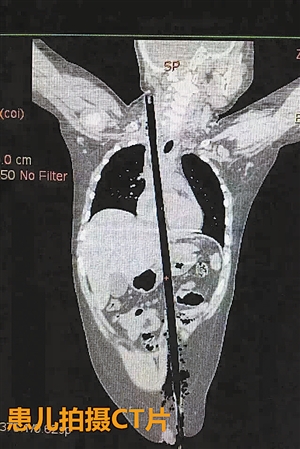

2月24日19时许,十岁男孩小郑从高处坠落,一支长约63cm,直径约1.5cm的竹棍不慎从他的左侧大腿根部插入腹腔并入胸腔直至右侧颈部,孩子疼痛难忍,命在旦夕。

事发后,小郑父母紧急将他送至龙岗区第三人民医院,经过检查后确诊胸腹联合伤,竹棍穿透患儿心脏,病情危重。由于条件所限,孩子由救护车转送到了深圳市儿童医院。